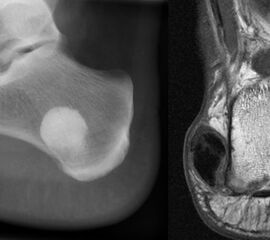

Sobald eine osteolytische Knochenläsion des Calcaneus erscheint, ist eine weiterführende Abklärung mittels MRT indiziert. Das intraossäre Lipom des Calcaneus lässt sich im Röntgen nur dann von der simplen Knochenzyste unterscheiden, wenn zentrale, dystrophe Verkal­kungen vorliegen (Abb. 25). Diese auch als Nidus oder Sequestrum bezeichneten Kalzifi­kationen sind typisch, jedoch nicht obligat für das intraossäre Lipom.

Axiale CT-Aufnahmen eines Osteoidosteoms im Bereich des Calcaneus mit typischer Nidusbildung und perifokaler Sklerose (links). Bildgesteuerte Thermofrequenzablation der Läsion (rechts).